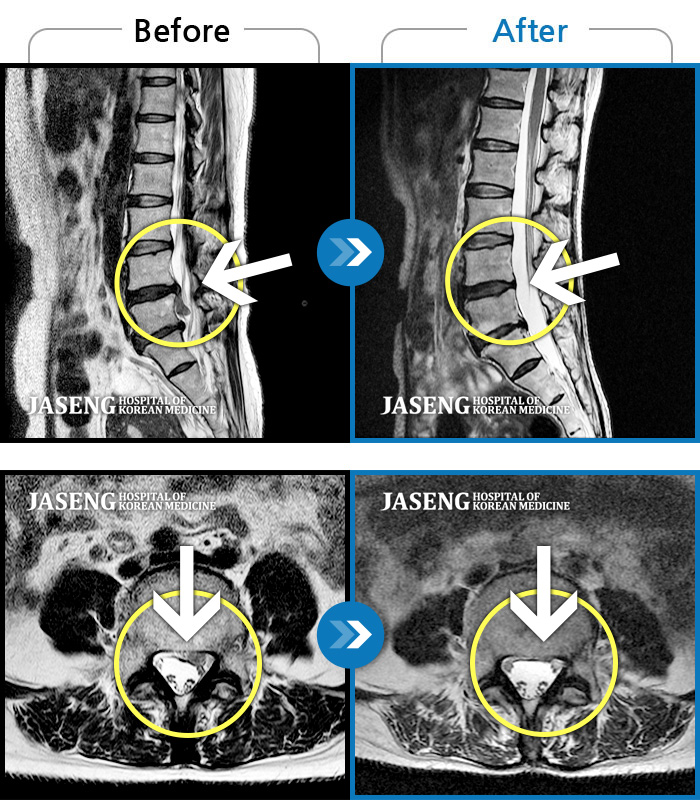

ȯںп Ǹ ǿ ԿǾ, ο ġ ۿ Ƿ ġḦ Ͻñ ٶϴ.